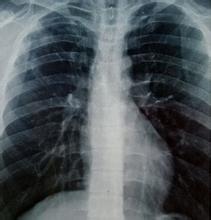

强直性脊柱炎由于治疗过程复杂治疗难度大让很多患者头疼不已,去医院也被繁杂的诊疗检查项目弄得头晕目眩。了解检查项目很有必要。那么,强直性脊柱炎的治疗需要做哪些检查?哪些检查有用?东北知名强直诊疗专家史东教授为大家答疑解惑。 史东主任表示:强直性脊柱炎的检查必须做到精细化,准确定位强直病根炎症。下面就强直检查做一个具体分析。 具体检查项目 1.X线检查:脊柱的X线片表现有椎体骨质疏松和方形变,椎小关节模糊,椎旁韧带钙化以及骨桥形成。晚期广泛而严重的骨化性骨桥表现称为“竹节样脊柱”。可通过X线透视反映。 2.CT检查:强直累及部位包括骶髂关节病变以双侧,且以关节滑膜部(下2/3)髂骨侧受累多见。可通过CT检查看出软骨钙化及关节间隙改变情况。 3.MRI检查:骶髂关节改变的MR表现是强直病情发展的重要指标。MR显示的关节软骨异常为软骨线影变窄、扭曲和中断。骨髓水肿以髂骨侧略多见 ,表现为局限或弥漫性片状 T1WI低信号,T2WI、STIR为高信号影。 1、检查炎症:检查关节、脊柱炎症分布,以及炎症对关节骨质的损伤程度。 2、检查免疫:检查强直患者免疫指数,针对性调节免疫,阻断病情复发。 3、检查微循环:检查关节、脊柱局部微循环堵塞情况,后期针对性祛炎通养。 4、检查体质:检查强直患者体质分型,做到针对性调理,增强免疫抗病能力。 5、HLA-B27检查:90%的强直性脊椎炎患者其HLA-B27抗原表达为阳性,普通人群中仅5-10%的为阳性,而强直性脊椎炎由于症状与许多疾病相似而难以确诊,因此HLA-B27的检测在病中的诊断中有着重要意义。 沈阳保髋强直医院是东北地区强直性脊柱炎专业研究院,省医保定点医院,专科专业四项检查免费,汇聚京沪辽三甲专家团队,帮助患者精准定位强直病情,为治疗康复打下坚实基础。 友情提示:强直性脊柱炎的检查要有针对性,不同患者不同病情需要的检查不同,要具体情况具体分析。如果对于强检查还有其他疑问可以点击【在线咨询】或拨打健康热线【024-3165 7599】咨询。